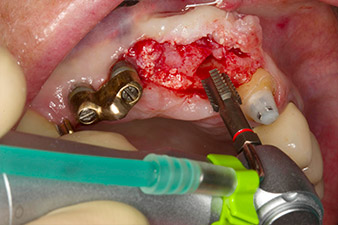

Nach primärer Abheilung werden die Weichgewebe mithilfe der basal unterfütterten Brücke ausgeformt. Zwei Monate später erfolgt die Freilegung mit einem leicht palatinal gelegten Kieferkammschnitt (Abb. 2).

Der Alveolarknochen erweist sich an Position 22 als ausreichend dimensioniert. Die Abbildungen 2 und 4 zeigen die Implantatbett-Aufbereitung, den Gewindeschnitt und die Implantation mit dem Implantmed.

Pilotbohrung mit dem neuen Implantmed und dem Winkelstück WS-56 L

Abb. 2: Zwei Monate später erfolgt die Pilotbohrung mit dem neuen Implantmed und dem Winkelstück WS-56 L (Programm P1, Übersetzung 1:1). Die Kühlung erfolgt über das links positionierte Sprayrohr (für Rechtshänder).